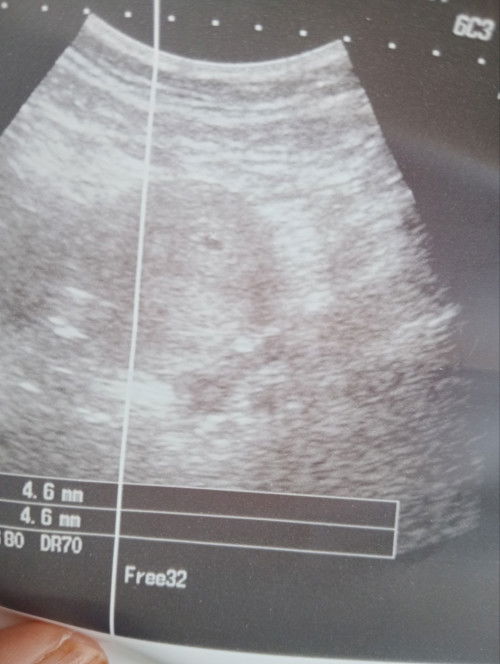

Scan tapi doc xpasti kantung atau pun x sbb terlalu kecik mesin xblh baca

Hai. Haritu ada post psl 24.4 positif samar2. Hrini upt lg.. tp terang . Pergi klinik kerajaan sbb xtahan tubuh mudah lembik plus berdebar2 sampai ketar tgn. Loya pon blh tahan cuma x muntah. Doc scan ada satu kcik tp xpasti kantung atau apa sbb trllu kcik Dan mesin xblh nk baca. Risau nya Sy. Sy tkt xde bby.doc ckp susah nk detect sbb period Sy xtratur. Mcm mna ye